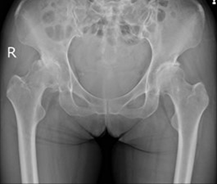

- 術前X線像

- ロボットTHA後

- 右:

高度脱臼股

の

関節症

左: 骨盤骨切り後股関節症

- 同日両側ロボットTHA後